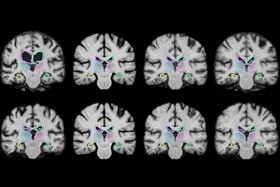

موسسه فناوری ماساچوست(MIT) یک سیستم عکسبرداری سریع پزشکی ابداع کردهاند که تصویرهای 3 بعدی را با سرعت 1000 برابر نسبت به قبل تحلیل و به پزشکان در حین عمل جراحی کمک میکند.